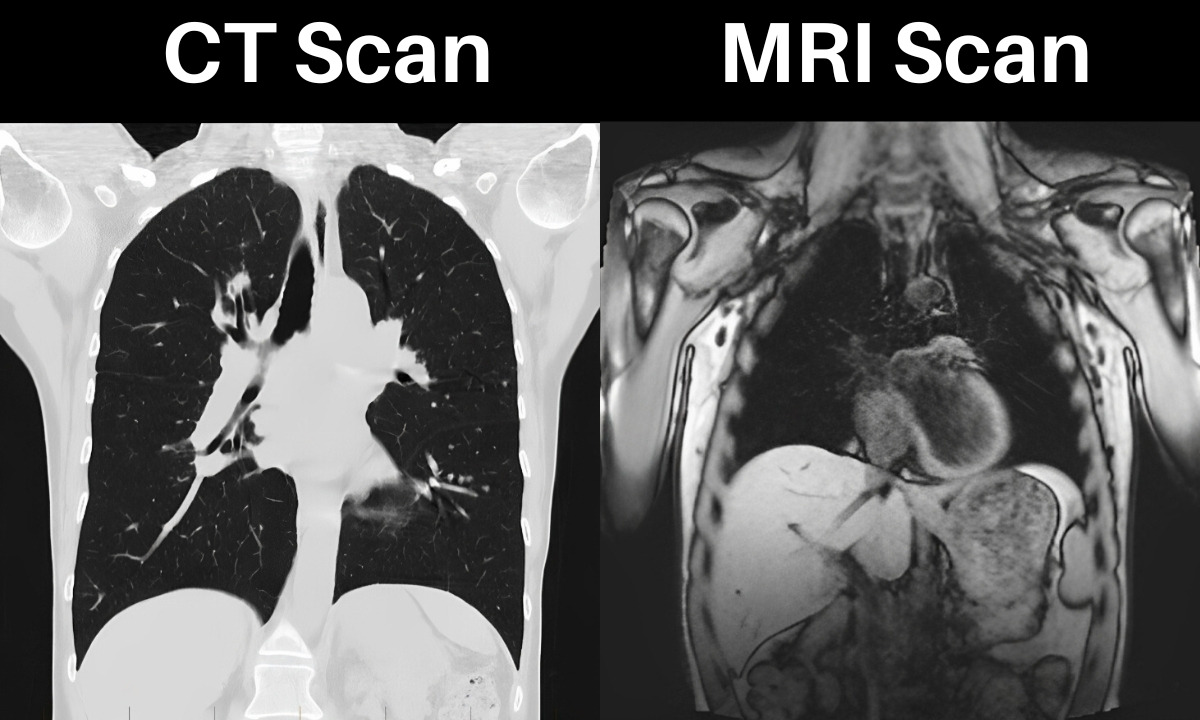

의학 이미징 기술은 현대 의학에서 필수적인 역할을 하며, 가장 흔히 사용되는 두 가지는 MRI(자기공명영상)와 CT(컴퓨터 단층촬영)입니다. 두 기술은 모두 인체 내부를 시각화하는 데 사용되지만, 작동 원리와 사용 목적, 장단점에서 차이가 있습니다. 이 글에서는 MRI와 CT의 기본 원리와 각 기술의 특성을 이해하고, 상황에 따라 어떤 기술이 적합한지 알아보겠습니다.

CT는 X선을 다양한 각도에서 투사하여 인체 단면의 이미지를 생성합니다. 이 데이터는 컴퓨터를 통해 3D로 재구성됩니다. CT는 밀도 차이를 기반으로 뼈와 내부 장기를 선명하게 보여줍니다.

- 밀도 차이 강조(뼈, 폐, 혈관 등)

CT는 빠른 촬영과 명확한 뼈 구조 평가가 필요한 경우에 유용합니다.

- 흉부: 폐렴, 폐암, 폐색전증